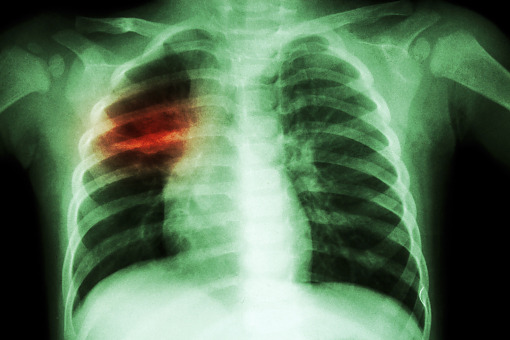

Gruźlica jest chorobą zakaźną powodowaną przez prątki z grupy Mycobacterium tuberculosis complex. Najczęstszą postacią gruźlicy jest postać płucna, a postać pozapłucna może atakować m.in. węzły chłonne, układ moczowo-płciowy, układ kostno-stawowy i ośrodkowy układ nerwowy.

Gruźlicą można się zarazić poprzez bliski kontakt, na przykład długotrwałe przebywanie w pomieszczeniu z osobą, która kaszle, odksztusza, mówi lub głośno się śmieje. Wtedy prątki gruźlicy krążą w powietrzu i – wraz z ich wdychaniem – dochodzi do zakażenia. Szczepionkę przeciw tej chorobie wynaleziono w 1921 r.